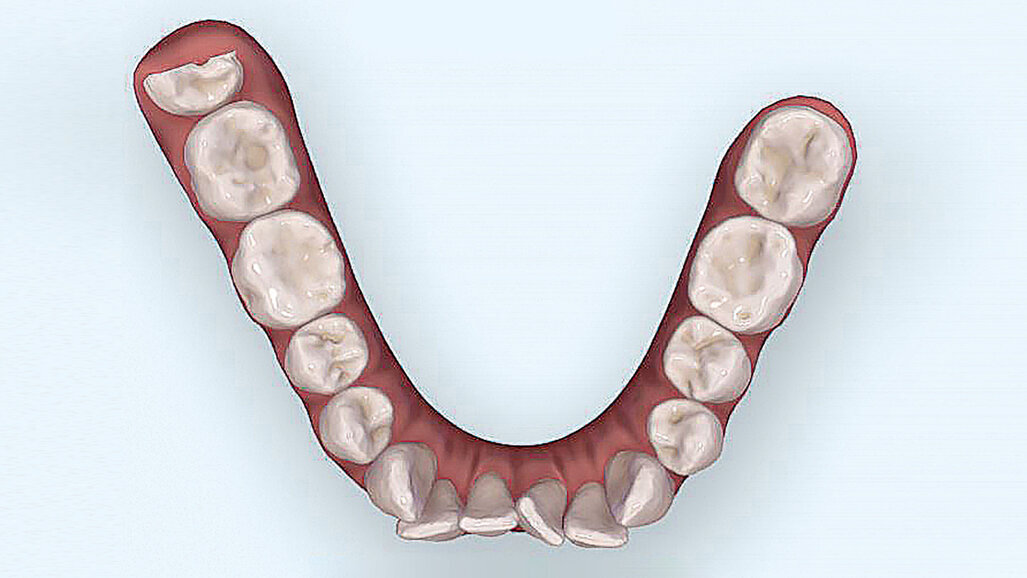

Vyšetřením jsme zjistili výrazný nedostatek místa v horní i dolní frontě. Zub 12, s meziodistální šířkou 6,25 mm, byl eruptován vestibulárně zcela mimo zubní řadu se současným posunem horní středové linie doprava. Mezera mezi zuby 11 a 13 činila 1,5 mm. Nedostatek místa v dolním zubním oblouku činil 2,6 mm resp. 2,85 mm ve dvou dolních kvadrantech. V transverzálním rozměru byl oproti normě menší jak anteriorně, tak i posteriorně. Oproti tomu skus laterálně a v místě špičáků byl normální – zde jsme diagnostikovali I. třídu podle Anglea. Hloubka skusu byla 0,5 mm s tendencí k otevřenému skusu. Incizální schůdek byl 0 mm se skusem hrana na hranu u zubů 11/41 a 21/31/41. Podle Boltnových indexů byl přítomen nepoměr v šířce zubů s přebytkem „zubního materiálu“ v dolní čelisti (obr. 3–5). Při skeletální diagnostice jsme nalezli disharmonii ve velikosti čelistí s retrognátní horní čelistí a ortognátní mandibulou – III. skeletální třída s úhlem ANB -2,3° a hodnotou WITS o velikosti -3,9 mm. U vertikální analýzy byl zřejmý mírně horizontální typ růstu s hodnotou SpP/MeGo 23° a poměrem SGo/NMe 71 % na základě anteriorní inklinace horní čelisti. Interincizální úhel byl lehce zvětšený, což bylo dáno mírnou protruzí horních řezáků spolu s retrudovaným postavením dolních řezáků (obr. 6, 7).

Pomocí skeneru iTero (Align Technology) byl proveden digitální sken výchozí situace chrupu pacientky. V simulátoru výsledků Invisalign může být názorně ve 3D prezentována aktuální i výsledná situace, čímž se, podle mých dosavadní zkušeností, dají velmi snadno rozptýlit pacientovy obavy. Zpravidla se tím zvyšuje i míra spolupráce pacienta. V tomto případě se podařilo pacientce zprostředkovat rozsáhlý a srozumitelný náhled na průběh a výsledek léčby, díky čemuž se viditelně oprostila od strachu, zda se konečný výsledek nebude příliš lišit od její představy (obr. 8–10).

Pomocí software ClinCheck a OrthoCAD (Align Technology) bylo na počátku naplánováno 64 fólií. Jako podpůrná terapie byl pacientkou denně po dobu 10 minut používán přístroj OrthoPulse (Biolux Research). OrthoPulse pracuje na základě Low-Level-Light-Therapy (LLLT), při které se využívá infračervené světlo o nízké intenzitě (600 až 1000 nanometrů).

Po primární sérii dlah byly potřeba dva refinementy. Postupně bylo použito dalších 25 a 14 dlah v obou čelistech. Pomocí celkem 103 dlah ve třech sériích byla celá terapie úspěšně dokončena za méně než 14 měsíců. Na konci léčby bylo dosaženo jak funkčního, tak esteticky optimálního výsledku. Správné postavení frontálních zubů a harmonizace středových linií odpovídaly simulaci výsledku, kterou jsme pacientce představili před začátkem léčby. Pacientka byla naprosto spokojena (obr. 11–17).